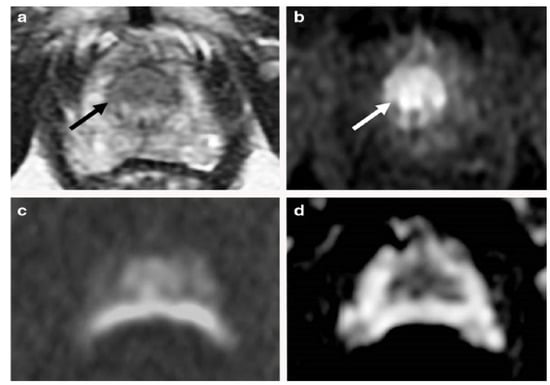

Various studies have used mp-MRI to diagnose PCa and have noted its diagnostic performance. Two examples of mp-MRI diagnostic performance are shown in Figure 1 and Figure 2 [34]. Di Campli et al. [35] conducted a study on mp-MRI to determine the diagnostic accuracy of PCa. A total of 85 patients underwent prostate MRI investigation at a 1.5 T MR system without an endorectal coil. In this study, the MR images were separately interpreted by three radiologists with 7 (reader 1), 3 (reader 2) and 1 year(s) (reader 3) of experience in prostate MRI, respectively (according to Prostate Imaging Reporting and Data System (PI-RADS) version 2). The sensitivity (CI 95%), specificity (CI 95%), area under the curve (AUC), and accuracy values for readers 1, 2, 3 were obtained (97.2% (90.3–99.7%), 88.9% (79.3–95.1%), 83.3% (72.7–91.1%)), (61.5% (31.6–86.1%), 23.1% (5–53.8%), 46.2% (19.2–74.9%)), (0.72, 0.70, 0.54), and 90.58, 78.82, and 77.64, respectively [35].

Figure 2. An example of mp-MRI diagnostic performance in a 62-year-old man with PSA 6.04 ng/mL. The DWI (a) and ADC maps (arrows) (b) showed a mild restricted diffusion in the bilateral base PZ. Unclear signal intensity on the T2WI (c) and a diffuse wedge-shaped enhancement on the DCE-MRI (d), imagined showing an inflammatory change. A systematic TRUS biopsy was performed with negative cores. “Reprinted with permission from Ref. [34]. 2020, Springer”. More details on “Copyright and Licensing” are available via the following link: https://link.springer.com/article/10.1007/s00330-020-06782-0 (accessed on 12 March 2020).